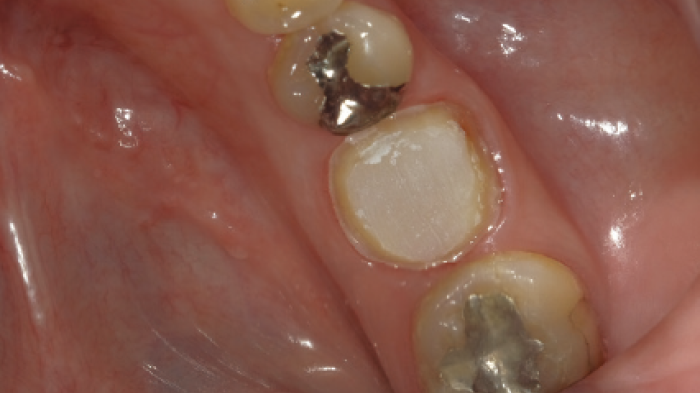

Une vue après le retrait de la restauration provisoire et du ciment temporaire. On peut observer qu'une partie du ciment temporaire reste encore sur la surface proximale distale.